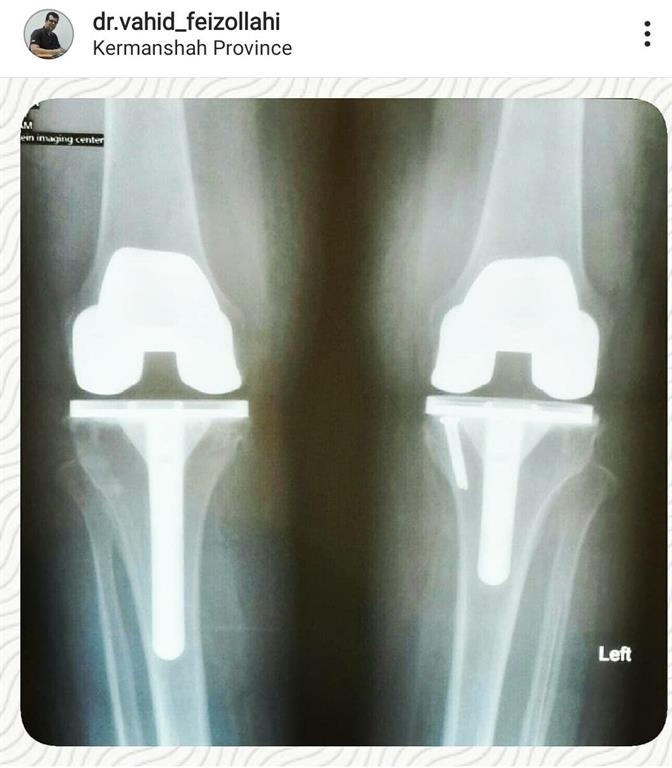

1. A 70-year-old woman

The patient was a 70-year-old woman with severe osteoarthritis that lead to her inability to stand up and walking and movements and knee deformity , which was performed simultaneously with bilateral knee replacement of the right and left knees, and was started by the patient's walker the day after surgery.